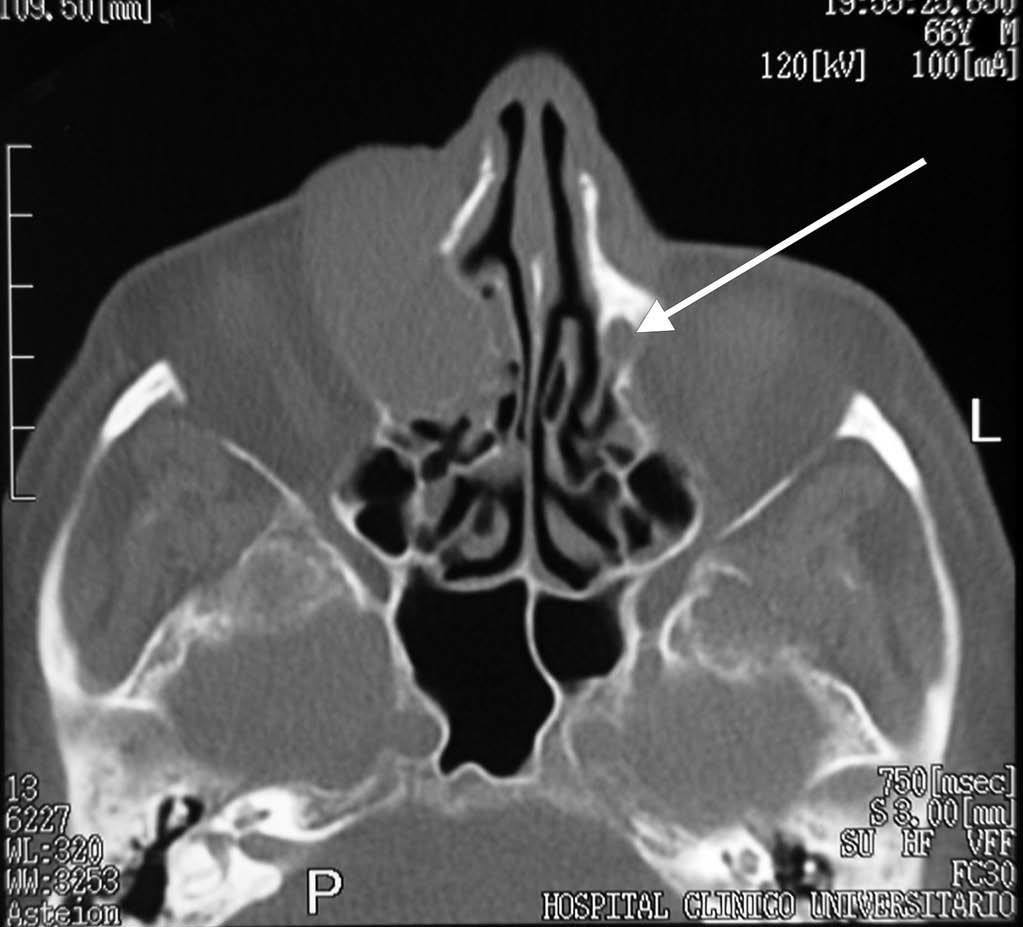

Se le realizó una TC orbitaria (figs. 1 y 2), sin administración de contraste intravenoso y se obtuvieron imágenes en los planos axial y coronal, con algoritmos de reconstrucción de partes blandas y de hueso. Se visualizaba la tumoración como una masa de partes blandas de densidad homogénea, morfología ovoidea, bordes bien definidos y contornos regulares, de 4 x 3 centímetros de diámetro anteroposterior y transversal respectivamente, localizada en el canto interno de la órbita derecha, que ocasionaba desplazamiento lateral del globo ocular y de la musculatura extrínseca ocular, con ensanchamiento del conducto lacrimonasal, que orientaba hacia un origen en el saco lacrimal. Se asociaba remodelación de las celdas etmoidales anteriores, sin evidenciarse signos de destrucción del hueso, ni afectación de estructuras vecinas.

Fig. 2.--Tomografía computarizada orbitaria, plano axial sin administración de contraste intravenoso. Corresponde a un plano más caudal que la figura 1, con algoritmo de reconstrucción de hueso, en la que se observa la masa descrita, adyacente a la pared medial de la órbita derecha, que produce remodelacón ósea de las celdas etmoidales anteriores vecinas, sin evidencia clara de destrucción del hueso. Conducto lacrimonasal izquierdo (flecha blanca).